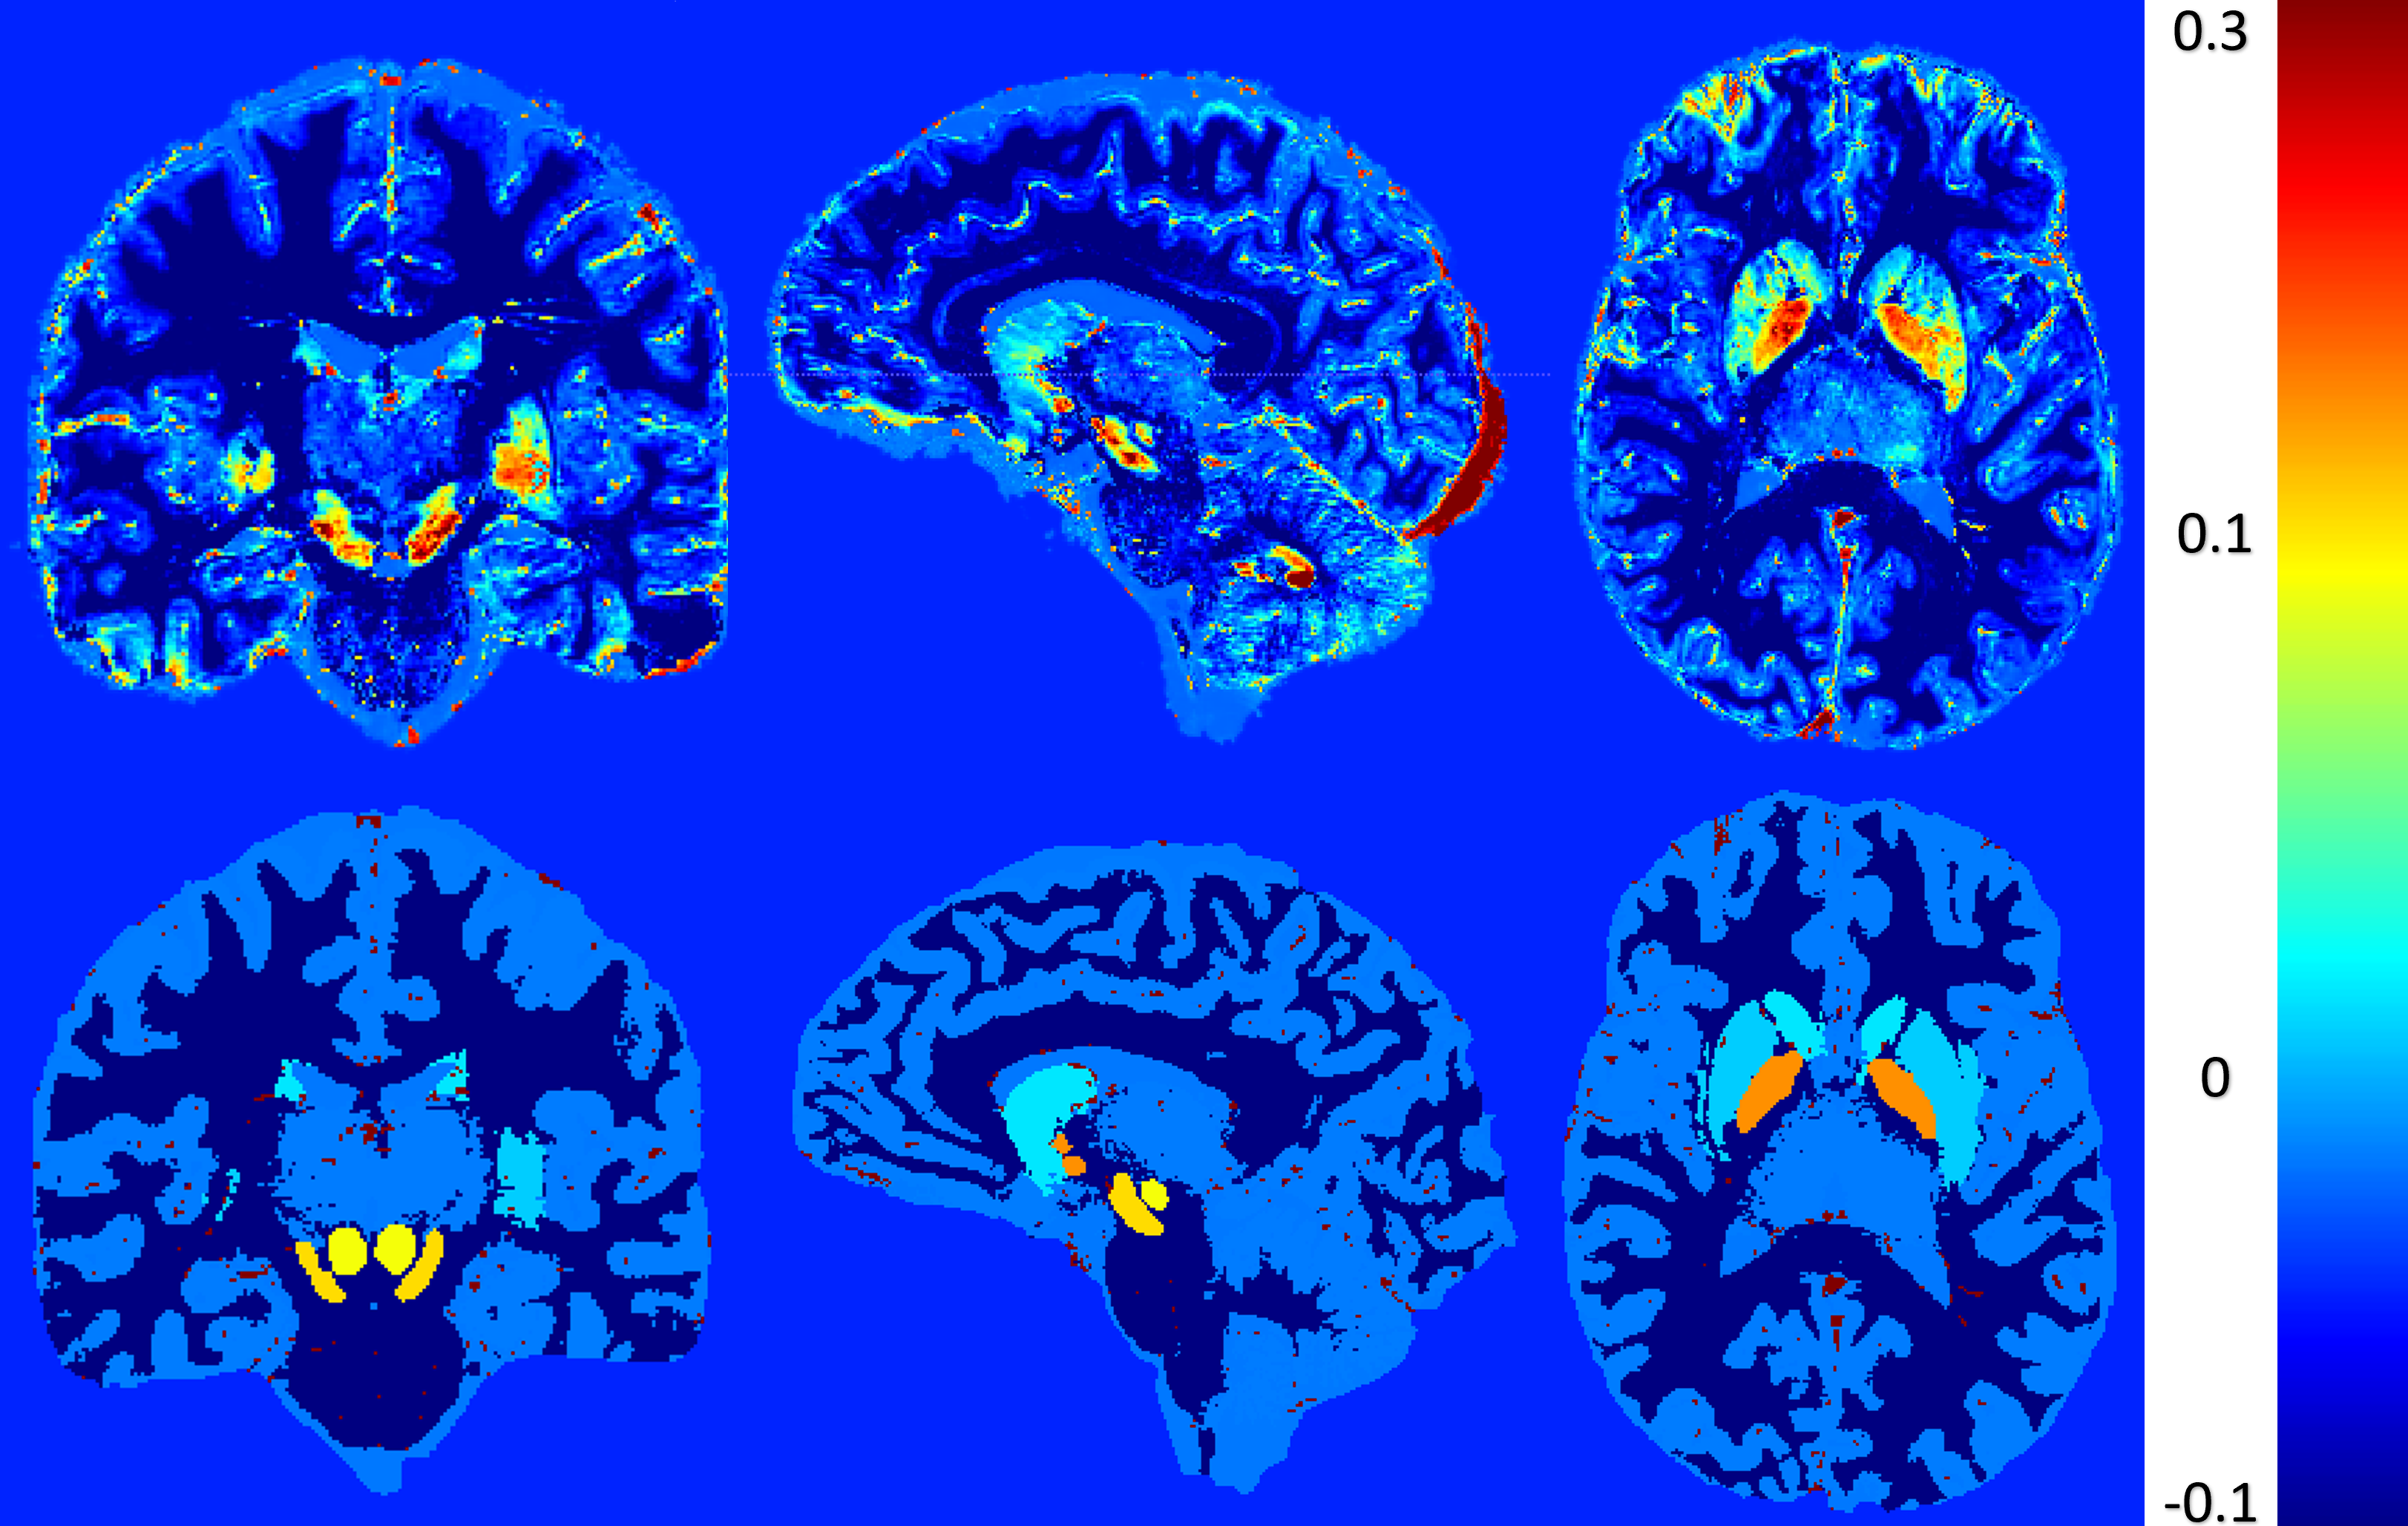

The first model was a binary classification task distinguishing between epileptic patients and healthy controls based on cortical morphometric features extracted from T1-weighted MRI using FreeSurfer. The classifier achieved promising results, with a receiver operating characteristic (ROC) curve showing a clear separation between the two groups. The area under the curve (AUC) was approximately 0.85, indicating that the model was able to effectively capture structural differences associated with epilepsy.